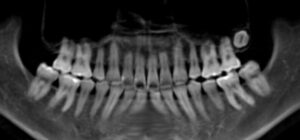

✅ 親知らずの有無をレントゲンで確認

✅ 埋伏歯(骨に埋もれている歯)の有無

✅ 顎のスペースに余裕があるか

✅ 今後動き出すリスクがあるか